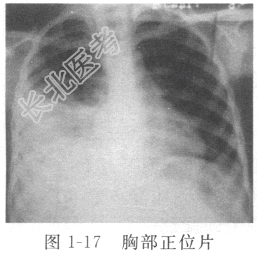

- [材料题] 患者女性,48岁,农民,因“咳嗽伴胸痛1个月,发热、胸闷4天”入院。患者1个月前无明显诱因出现咳嗽,多为阵发性干咳,咳嗽时伴有右侧胸痛,深呼吸时亦感胸痛,疼痛程度不剧烈,无咳痰、咯血、气急等不适,未予重视。4天前出现胸闷,左侧卧位时较明显,平卧或右侧卧位可稍缓解,伴有发热,多为午后低热,体温最高37.8℃,无明显畏寒、寒战,伴有乏力、纳差,就诊于当地卫生院,血常规提示WBC 8.2×109/L,N% 70.1%,L% 19.4%。口服双黄连口服液及解热镇痛片后,胸痛逐渐减轻,但体温仍未恢复正常,胸闷较前加重,遂就诊我院。查体:消瘦体型,右侧语音震颤减弱,右侧呼吸音减弱,心脏、腹部体检无异常。门诊胸部X线片(图1-17)示右侧胸腔积液,血沉70mm/h,PPD试验(+++),拟“胸腔积液”收入科。入院初步诊断:右侧胸腔积液(原因待查)。

患者中年女性,农民,病程不长,起病隐匿,有咳嗽、胸痛、胸闷等呼吸道症状,有午后低热、盗汗、乏力等全身中毒症状,胸部X线片示右侧胸腔积液,ESR偏快,考虑胸腔积液原因为结核性可能性大。入院后行胸腔穿刺,引出草黄色透明胸水600ml。胸水常规示李凡他试验阳性,比重1.018,白细胞1.28×109/L,单核细胞86%,多核细胞14%。胸水生化提示总蛋白44g/L,葡萄糖0.6mmol/L,腺苷脱氨酶(ADA)85U/L。胸水涂片见大量淋巴细胞,未见癌细胞。胸腔镜(图1-18)下见大量草黄色胸水,吸出后见部分胸膜粘连,胸膜炎性增生性改变,伴有粟粒样结节,活检钳夹取2块做病理学检查,结果显示小块胸膜组织有干酪样坏死、上皮样细胞及朗格汉斯巨细胞,符合结核改变。